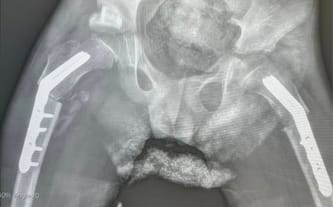

Dokładnie 13 kwietnia 2026 roku minął 39. dzień od dnia operacji w Paley European Institute, mieliśmy drugie kontrolne RTG, które potwierdziło, że wszystko jest dobrze! Główki kości udowych są tam, gdzie powinny, kości ud zrastają się poprawnie. Możliwe, że śruby i blaszki nie będą wyjmowane.